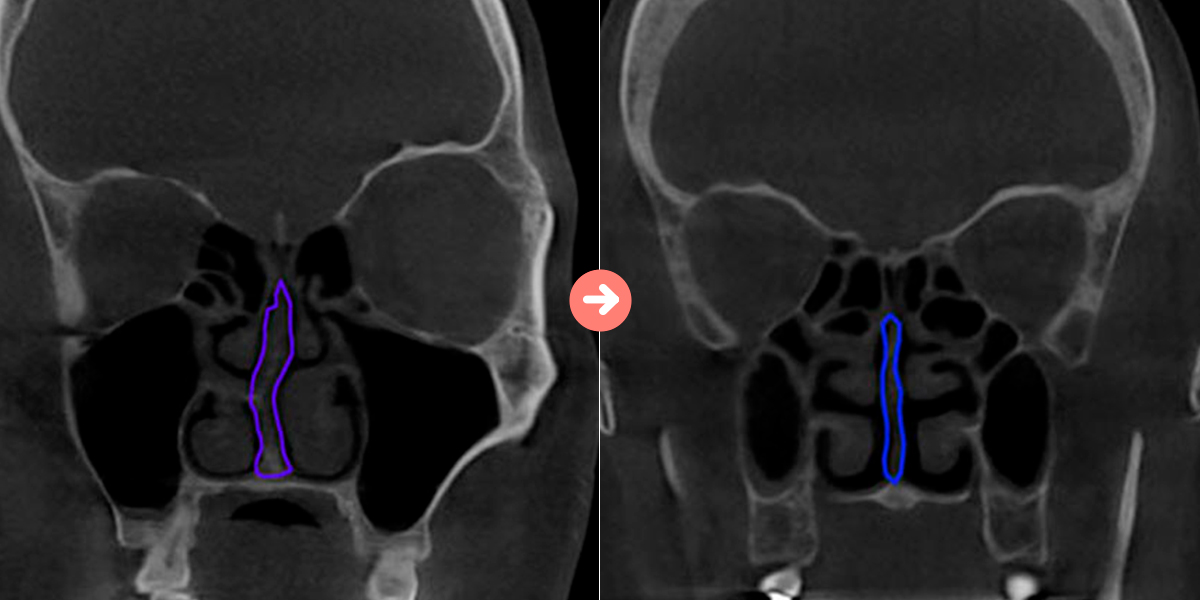

매부리코/휜코의대부분은 비중격만곡증을 동반하고 있습니다.비중격만곡증이 심한 경우 코 막힘 , 비염 , 축농증 등의 질병을 유발하여 일상생활에 불편함을 줍니다. 수술 전 비중격만곡증의 유무를 면밀하게 관찰하여 코 라인과 함께 비중격만곡증 개선을 도와 드립니다.

3D-CT

수술 전 철저한 분석으로 코의 외적인 부분 뿐만 아니라 코의 기능(비염,비중격만곡증,축농증 등) 도 생각한 수술